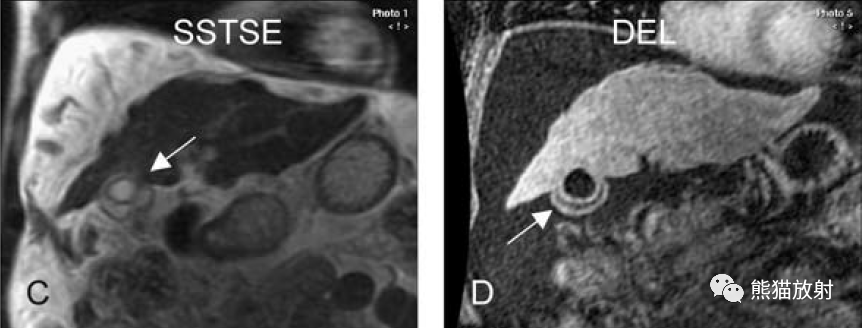

膽囊癌。A~D圖:上方層面,表現如上所述,形成腫物侵及肝臟。E、F圖:下方層面示膽囊壁不規則增厚,明顯不均質強化。

膽囊壁增厚(并肝硬化、門脈高壓、腹水)。T2WI顯示膽囊壁因水腫而光滑均勻增厚,增強延遲期顯示強化的膽囊壁(內外兩層:粘膜層和漿膜層),薄而清晰光滑。

T2壓脂(T2 fatsat):膽囊窩內膽囊癌病變較肝臟為高信號,病變頂部向肝內擴展;

增強動脈期(ART):不均質強化;

延遲期(DEL):部分廓清,部分持續強化。